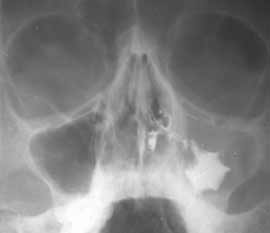

1 2

Рис. 2. Полипозный верхнечелюстной синуит слева. (Слева) Обзорный снимок. (Справа) Синусограмма.